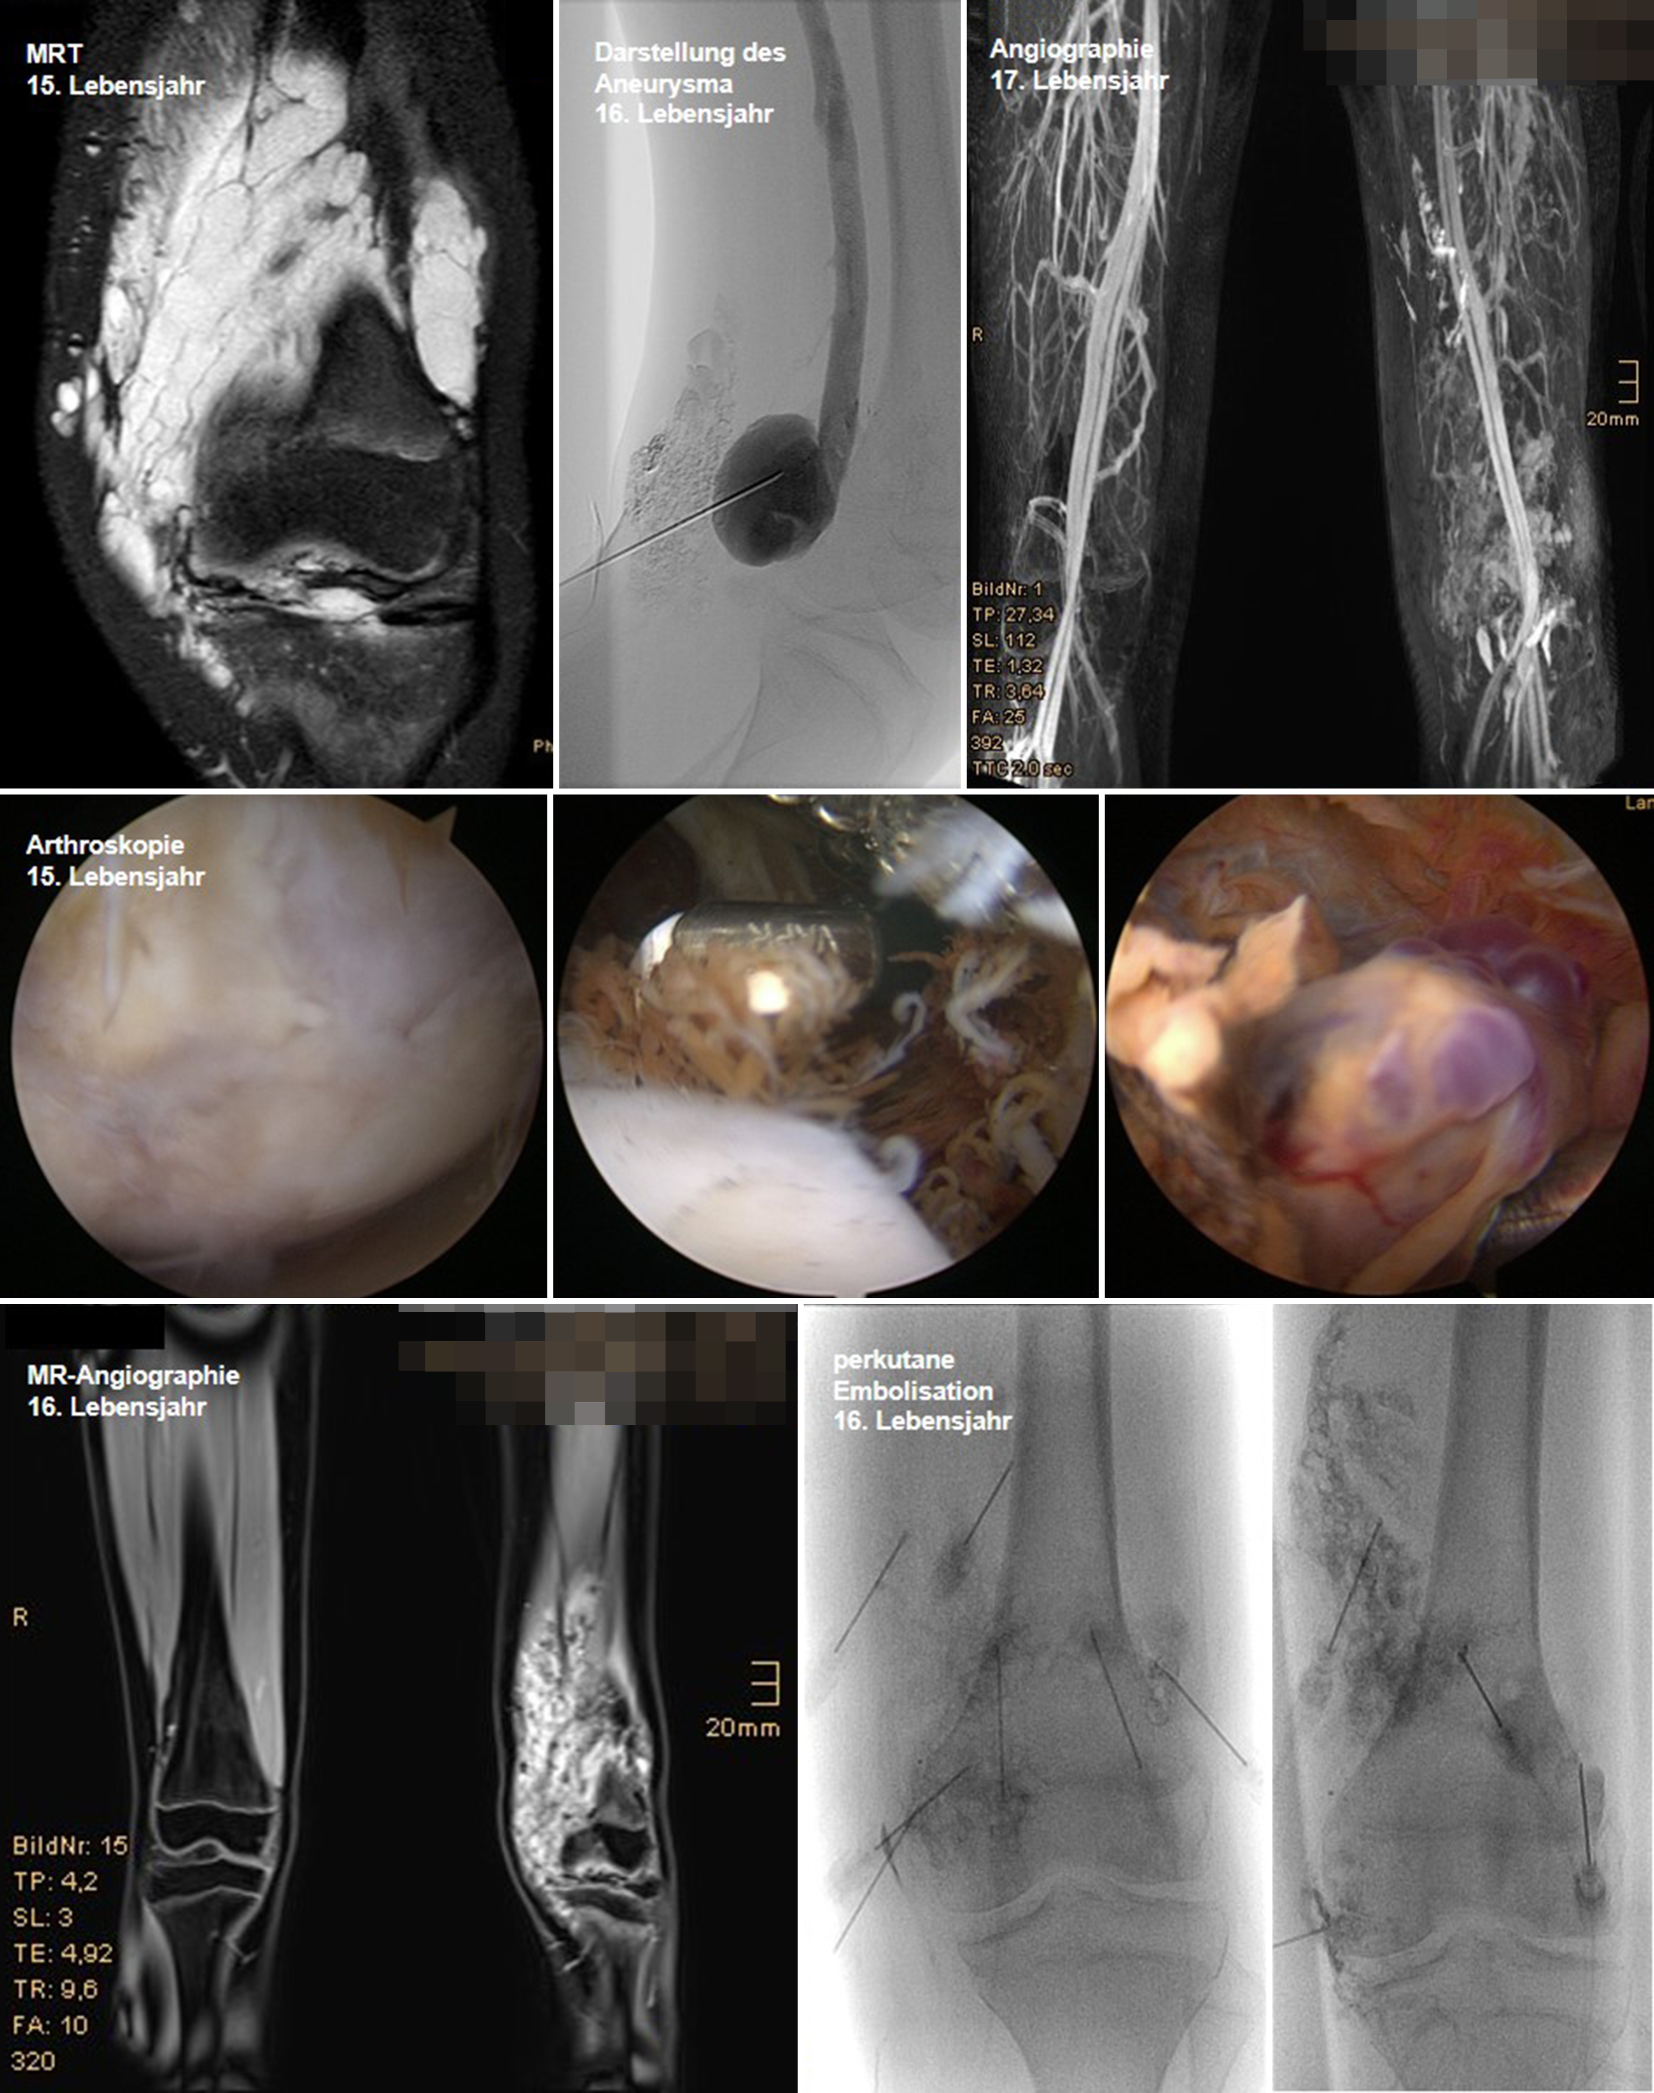

Venöse Malformationen

Im März 2017 wurde ein 15-jähriges Mädchen mit Schwellung an distalem Oberschenkel und Kniebereich rechts seit etwa 2,5 Jahren vorstellig. Es besteht teilweise eine Bewegungseinschränkung. Im Alter von 16 Jahren Durchführung einer diagnostischen Arthroskopie, hierbei zeigte sich eine ausgeprägte Gonarthrose und Synovialitis. Eine Synovektomie und die Koagulation der intraartikulären Anteile der venösen Malformation wurden durchgeführt (Abb. 1).

Abb. 1

Fall 1: Patientin mit venöser Malformation (© SALK)

Im Verlauf wurde bei Schwellung und Schmerzen die Diagnose eines Aneurysmas der Vena poplitea gestellt. Dieses wurde im Alter von 16 Jahren gefäßchirurgisch bei 4 cm breiter Basis zur V. poplitea gerafft. Aktuelle Therapie: Die Patientin erhält zweimal wöchentlich Muskelaufbautraining und Lymphdrainagen, zusätzlich sind seit dem 15. Lebensjahr 11 Embolisationsbehandlungen erfolgt.